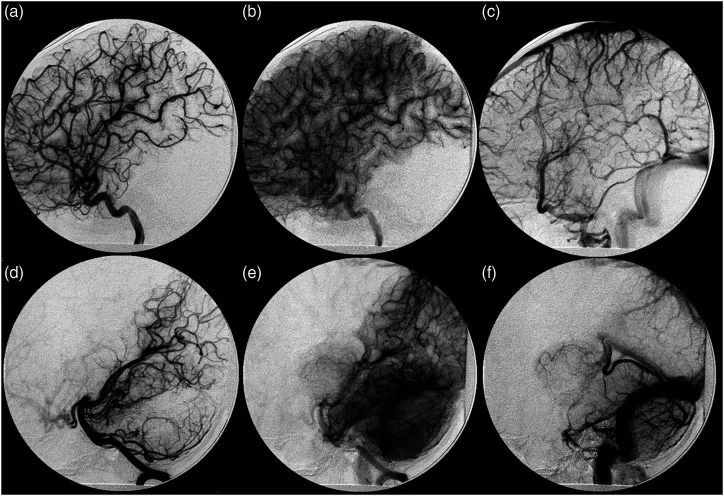

患者初期在5岁时出现右上肢(UE)震颤,经检查发现左丘脑病变,MR特征提示脑海绵状血管畸形(CCM),以及相关的发育性静脉异常(DVA)流入大脑内静脉(图2)。当时没有急性出血的证据。在初次诊断海绵状血管畸形时进行的脑数字减影血管造影显示没有脑动静脉畸形或任何其他分流血管病变的证据(图3)。为了治疗海绵状畸形,患者接受了伽玛刀手术(14Gy),导致右上肢无力。1年后,患者再次就诊,海绵状畸形部位出现少量脑实质内出血。

图3:初次就诊时的血管造影。